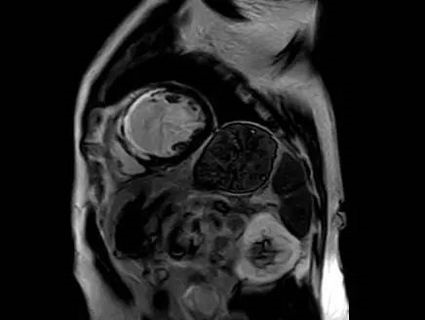

医生利用心脏磁共振检查观察心脏各组织情况,也可用于检查患者是否罹患以下疾病:1.先天性心脏病;2.非缺血性心脏病;3.缺血性心脏病;4.手术或外伤评估;5.瓣膜疾病;6.心包疾病;7.肿物。

1.心脏的解剖结构问题,比如:异常连接、分流、狭窄、外科手术前评估及随访,房间隔缺损、室间隔缺损、粘液瘤、血栓、心肌肥厚(流出道是否梗阻)以及增大或缩小的心腔等。

8.占位。比如:肿物范围、性质等。

2.心肌灌注成像,通过对比剂首过心肌的检测可以判断知否发生心肌灌注异常(心肌缺血)。

3.心肌活性评估,心肌组织中失去活性的心肌细胞和延迟强化存在可靠的对应关系,即失去活性的心肌组织有延迟强化。